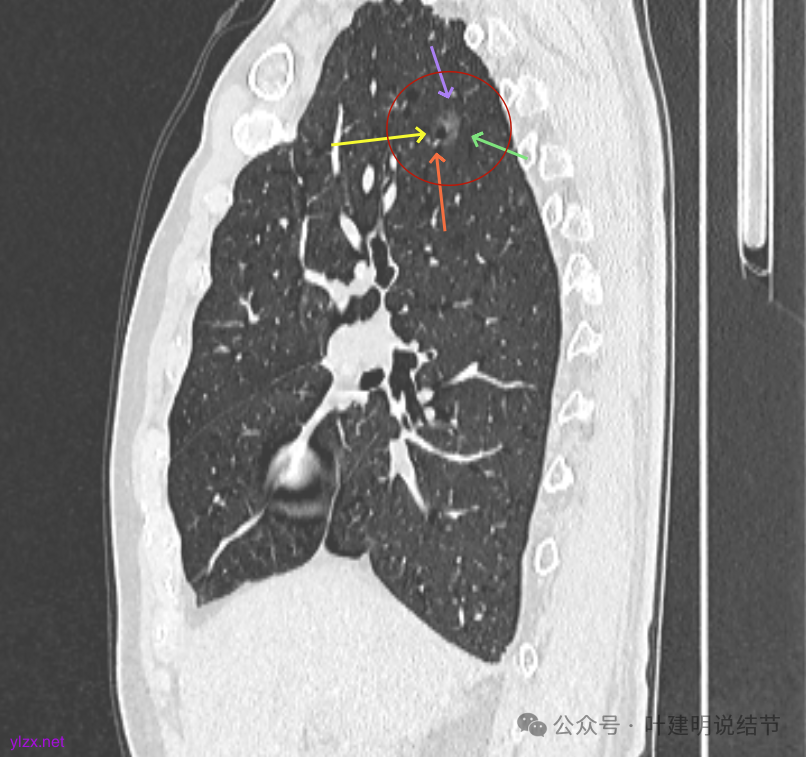

最后看2025年3月的连续层面的影像细节:

右上病灶淡磨密度,有空泡征,整体轮廓较清。

瘤肺边界清楚,空泡征明显。

表面不平,没有实性成分。灶内空泡有些像蜂窝状。

病灶边上有小血管走行,整体轮廓清,没有明显实性成分。

右上叶病灶有血管贴边,轮廓清;

矢状位见右上病灶也是纯磨,灶内的血管可见,表面部分有细毛刺,整体轮廓与边界清楚。

左上病灶矢状位见也是纯的,没有实性成分。